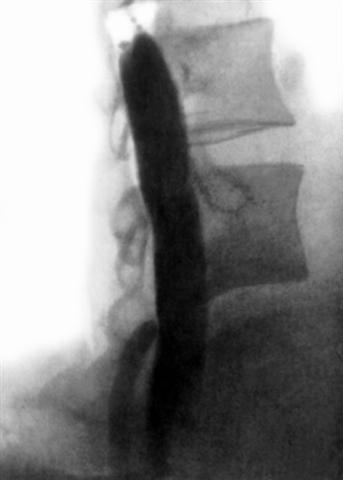

Рис. 4б). Миелограмма поясничного отдела позвоночника в норме: боковая проекция.